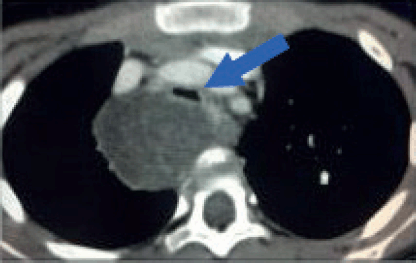

Figure 5. Tracheal compression. Contrast-enhanced axial CT image of a 6-year-old girl with a large tumour at the upper right posterior mediastinum. The lesion crosses the midline over the anterior surface of the vertebral body, at the level of the manubrium. Both, arterial and venous mediastinal great vessels are selectively enhanced with contrast. The trachea is severely compressed by the tumour (Blue arrow). This patient is at high risk of ventilatory collapse during the induction of anaesthesia.